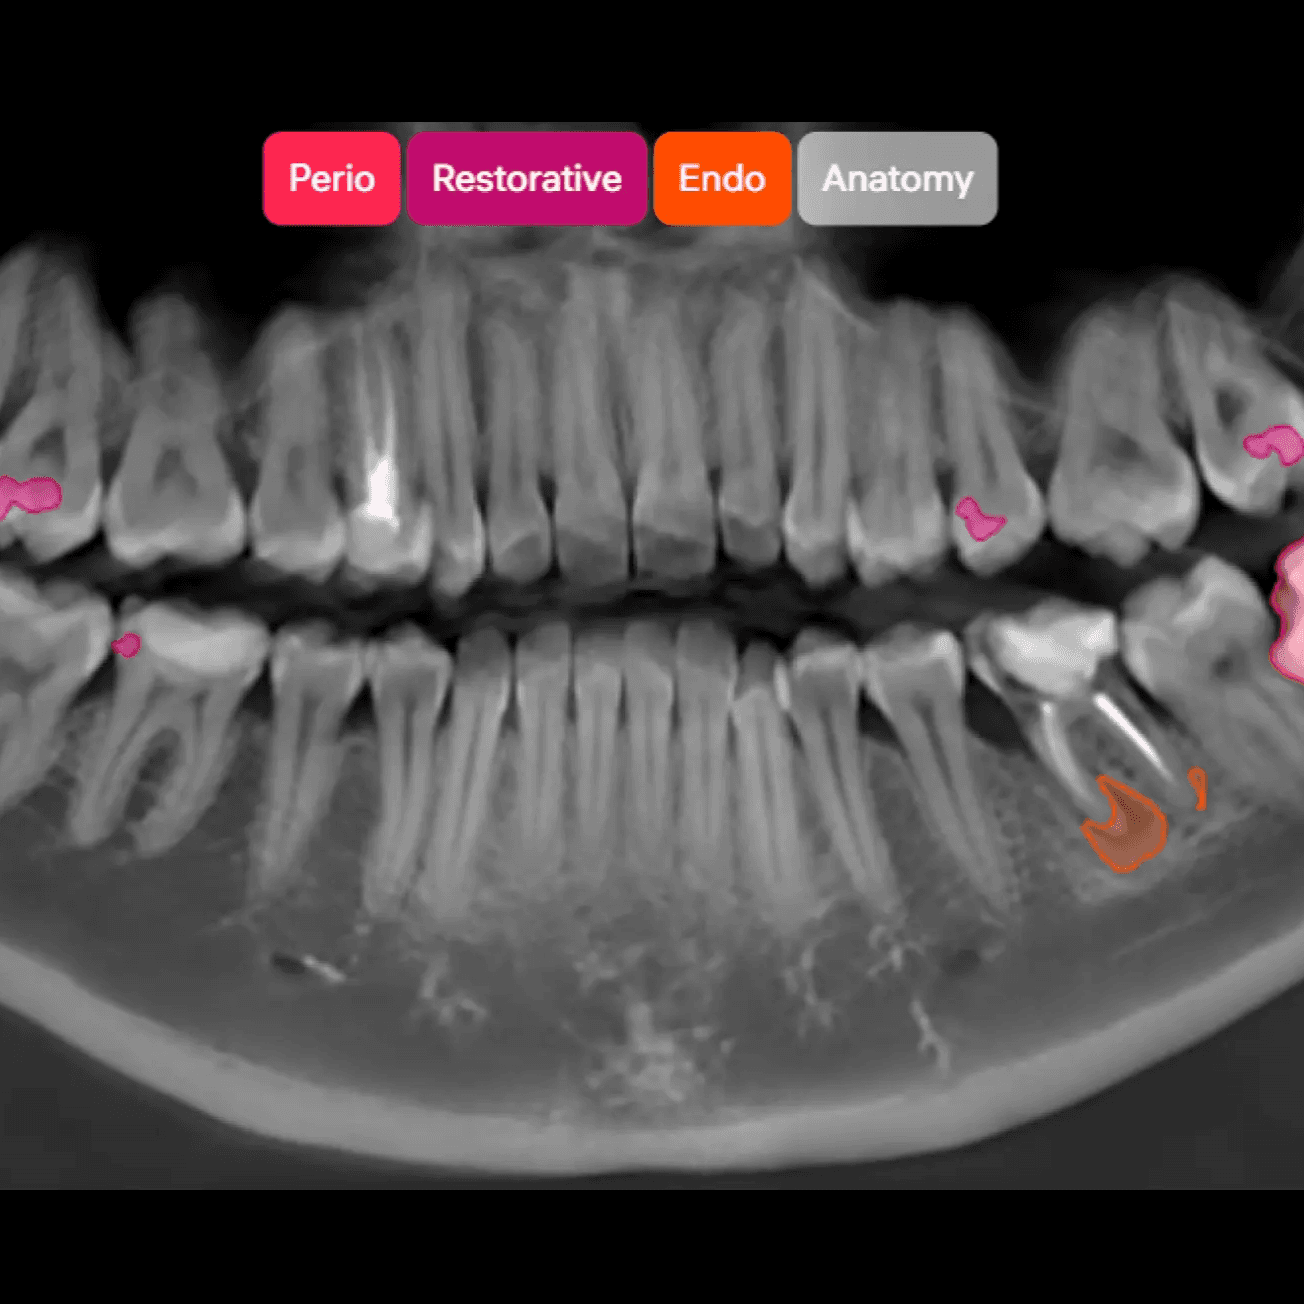

O DxPlan apoia diagnóstico e planeamento com análise por IA de imagiologia dentária 2D/3D, relatórios e visualização por dente — com decisão final sempre do profissional.

Capacidades Principais

Análise 2D/3D (CBCT) com deteção assistida por dente

Deteções assistidas de achados, organizadas por dente.

Relatórios 2D e 3D (CBCT) com medições, etiquetas por categoria e codificação visual